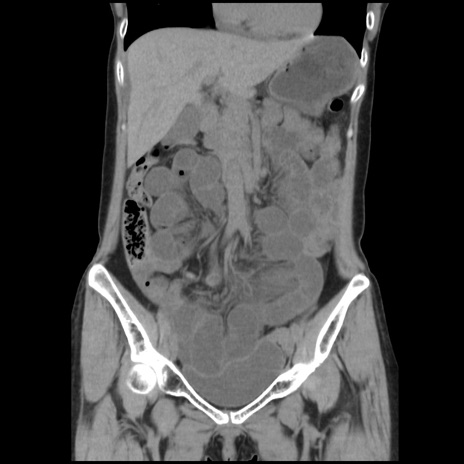

症例32(冠状断像)

【症例】40歳代 女性

【主訴】上腹部痛、嘔気・嘔吐

【現病歴】約9時間前頃から急に上腹部痛、嘔気、嘔吐が出現。改善しないため救急要請。

【既往歴】子宮頚癌(広汎子宮全摘術、放射線療法)、腸閉塞

【身体所見】腹部:平坦、軟、腸雑音亢進、上腹部を中心に腹部全体に圧痛あり。

【データ】WBC 8400、CRP 0.03